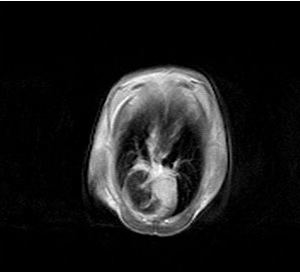

小动物核磁共振成像系列

核磁共振成像分析应用系列

上海寰彤科教设备有限公司主要专注于核磁共振成像技术以及NMR分析技术的创新和研发,是一家集测试、研发、生产、销售、服务为一体的磁共振产品制造企业。公司的产品广泛应用于医学影像、药物分析、生物医药等多个科研、教学领域,覆盖核磁共振波谱高分辨化学分析、磁共振成像等技术范畴,并拥有自主国产化的生产能力与独立的研发设计能力。

公司致力于医学成像类、核磁共振波谱分析设备制造研发,产品涵盖NMR、MR、成像类、波谱类设备,应用于生物、药物、材料,食品,化学等领域。目前已有永磁60/90MHz核磁共振波谱仪,永磁(1.5T)H/F/P多核小动物核磁共振成像与弛豫测量系统,低场核磁共振分析系统,清醒小动物体成分检测仪等多种科研分析产品。